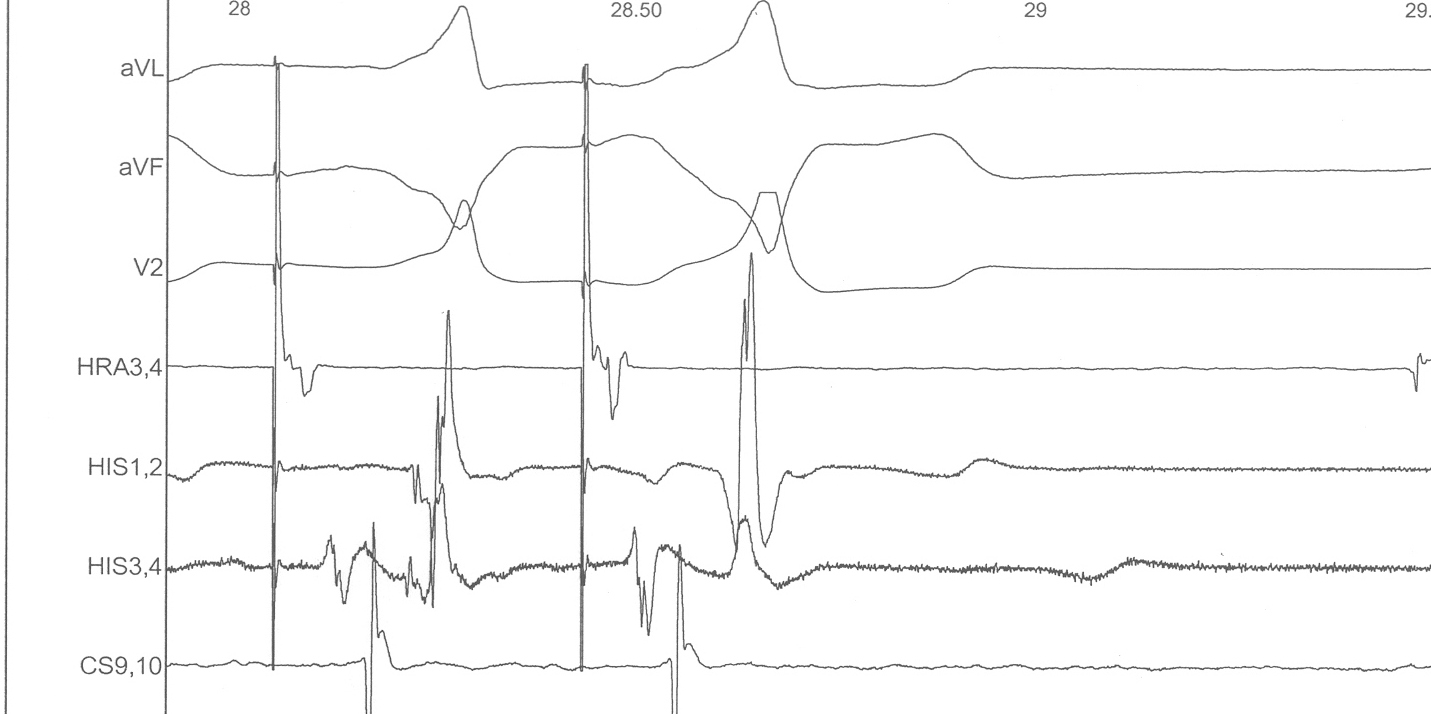

Narrow QRS tachycardia, 1:1 VA, central atrial activation, VA > 70 ms

svt.jpg